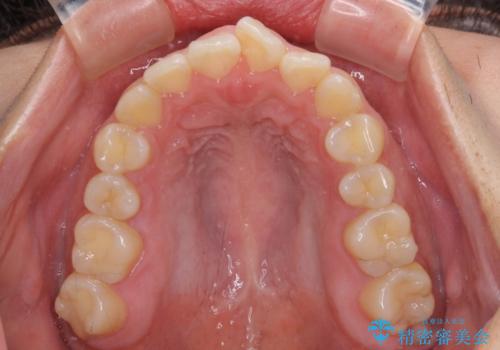

- 上下の前歯が非接触であることと、それに伴う口元の閉じにくさを気にして来院された患者様です。

奥歯の咬み合わせを見ると、上顎が下顎に対して相対的に前方にありました。

口元の閉じにくさを改善するためには、上顎臼歯を後方に移動させた咬み合わせにする必要があります。

インビザライン単体で改善することも可能ですが、達成する可能性が高くないため、カリエールディスタライザーという補助装置を併用して、より確実性を上げることとしました。

奥歯の咬み合わせを改善しながら、並行してインビザラインで歯列を整えることとしました。

カリエールディスタライザーを併用したことで、確実かつ短期間で治療を終えることができました。